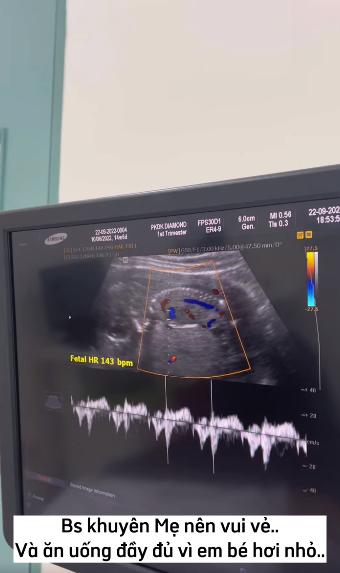

Bác sĩ khuyên mẹ nên vui vẻ và ăn uống đầy đủ vì em bé hơi nhỏ. Nghe xong câu đó, em cảm thấy có lỗi vô cùng cả nhà ạ.

Thấy con nằm vò đầu mà tim em như xé ra từng mảnh. Em phải làm sao giờ cả nhà, ăn gì vô con mấy chị nhỉ”, cô bật khóc nói.